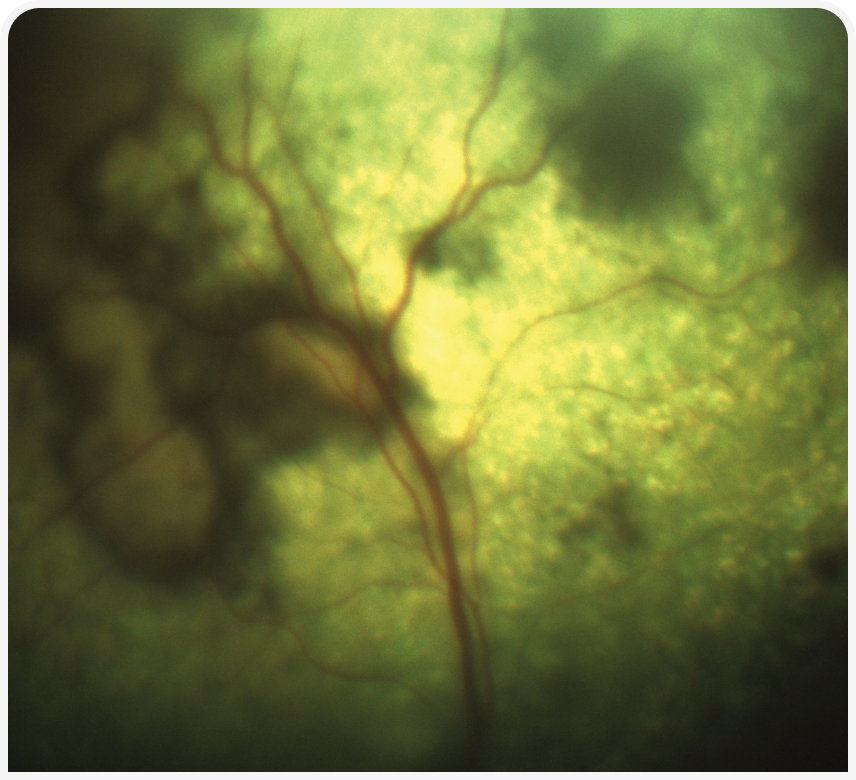

Часто в таких случаях бывает полезно повторить непосредственное обследование, поскольку исходно можно упустить из виду или не принять во внимание незначительные отклонения. Если ранее не определяли балльную оценку мышечной массы, следует сделать это и записать результат. Осмотреть ротовую полость у бодрствующей кошки часто непросто, но значимую патологию можно выявить уже при осмотре зубов и края десен. Однако важно иметь в виду, что беглый визуальный осмотр не позволяет исключить выраженного и клинически значимого заболевания зубов; тяжесть болезненных состояний, таких как резорбция корня зуба, можно определить только рентгенографически (Рисунок 1) (1). Следует провести тщательное офтальмологическое обследование для выявления симптомов увеита или хориоретинита. Эти симптомы неспецифичны, но часто наблюдаются у кошек при грибковых или протозойных инфекциях (Рисунок 2) (2). Нужно тщательно обследовать любые кожные или подкожные узелки, особенно в области внутренних парастернальных лимфоузлов. Также разумно понаблюдать за движениями кошки, чтобы выявить признаки заболеваний суставов, позвоночника или нервной системы; обычно кошек осматривают на столе и поэтому не замечают изменений походки, координации или силы мышц.